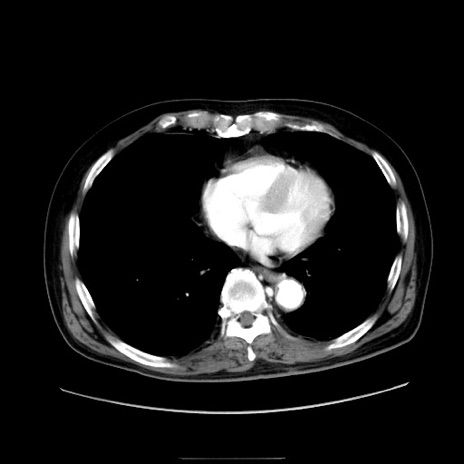

症例30(横断像)

【症例】80歳代男性

【主訴】臍周囲痛

【現病歴】約6時間前から臍下部痛が出現。次第に腹部膨隆・背部痛も生じてきたため来院。背部痛の場所は変化しない。

【身体所見】意識清明、BT 36.3℃、BP  131/87mmHg、P 87bpm、SpO2 100%(RA)、臍周囲自発痛・圧痛あり、反跳痛なし、自発痛部位に一致して板状硬あり、腹部膨隆、腸雑音減弱、CVA tenderness両側陰性。